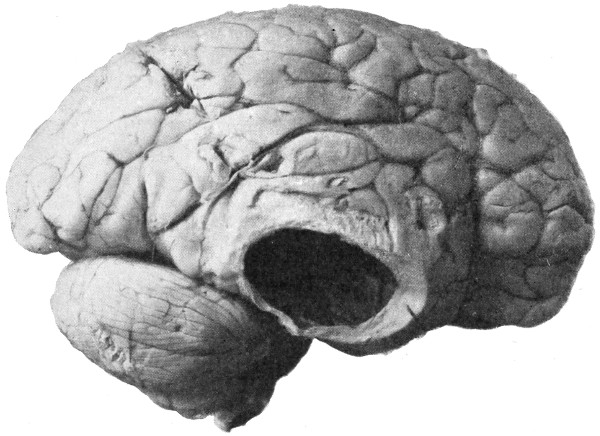

The child was 3 months old, and presented a tumour, the size of an orange, situated between the occipital protuberance and the nape of the neck. The mass was pedunculated, the stalk being about the size of a four-shilling piece in diameter. It was soft, translucent, irreducible, and swelled up on coughing. An attempt at removal was carried out, and, after incising the outermost layers, three ounces of cerebro-spinal fluid escaped. A second tumour was then found occupying the base of the swelling. This was also punctured, more fluid escaping. Both sacs were cut away and the wound sewn up. Death occurred on the third day, preceded by convulsions, retraction of the head and neck, and high fever. The autopsy showed that the fontanelles were widely open, the anterior measuring 4 inches from side to side and 212 from before backwards. The bones of the vault were markedly thinned. In the subdural space there was a quantity of fluid, and the cerebral substance was soft and diffluent, the convolutions flattened, and the ventricles distended. There was a broad gap in the occipital bone, extending downwards into the foramen magnum, and in this situation the cerebellum had bulged backwards into the protruding mass. (See Fig. 22).